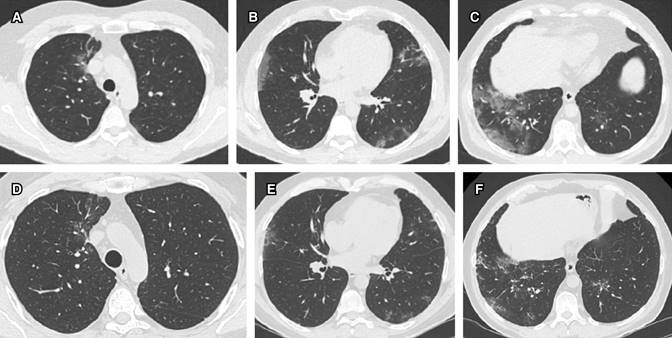

Las imágenes radiológicas mostraron patrón de vidrio despulido bilateral periférico, que evolucionó lentamente hacia la mejoría (Figura 1).

Figura 1: Evolución tomográfica del caso 1 en cortes axiales a tres niveles: A) apical, B) medio y C) basal al momento del diagnóstico, comparativamente con un control tomográfico realizado 20 días después a los mismos niveles de corte (D-F) con una obvia mejoría.